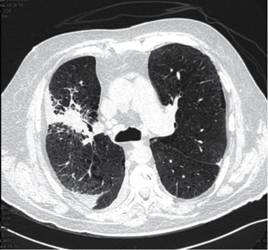

Paciente masculino de 64 años de edad, con antecedentes de importancia de hipertensión arterial sistémica, enfermedad pulmonar obstructiva crónica, hiperuricemia de larga evolución y enfermedad renal crónica de reciente diagnóstico. Se presenta al Servicio de Urgencias con cuadro gastrointestinal, fiebre, dificultad respiratoria con saturación de 70% al aire ambiente y disminución de volúmenes urinarios. Se realizan estudios de laboratorio en los cuales se hace evidente falla multiorgánica caracterizada por anemia y trombocitopenia; en el frotis sanguíneo se reportan mieloblastos y blastos, 5% en sangre periférica, con reacción leucoeritroblástica, elevación de enzimas hepáticas, elevación de azoados con anuria, persistencia de saturación de oxígeno baja (70-85%) a pesar de haberse proporcionado oxígeno suplementario por puntas nasales y posteriormente tienda facial a 10 L/min. Se decide realizar las TAC tóraco-abdominal con las siguientes alteraciones descritas en las Figuras 1, 2 y 3.